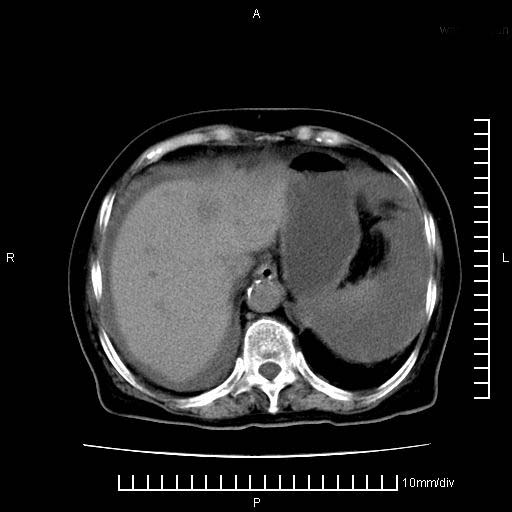

上腹疼痛月余,外院核磁诊断胰腺癌。现临床示右下腹可明显触及包块,可片子上怎么没有看到?

1。胰腺ca伴腹膜腔转移

2。肝左叶低密度灶,考虑转移可能

支持胰腺癌肝内转移,腹水改变。

1、考虑胰腺癌伴腹膜腔转移,胸腹水。

2、肝脏转移可能。

1)考虑胰腺癌并胰腺假性囊肿形成。2)肝内低密度灶,不排除转移。3)右肾盂积水。4)腹水。5)右侧胸腔积液并右肺下叶部分膨胀不全。

考虑胰腺ca伴腹膜腔转移、肝左叶转移、右肾积水。右胸腔积液。

考虑胰腺ca伴腹膜腔转移、肝左叶转移、右肾积水。右胸腔积液。支持